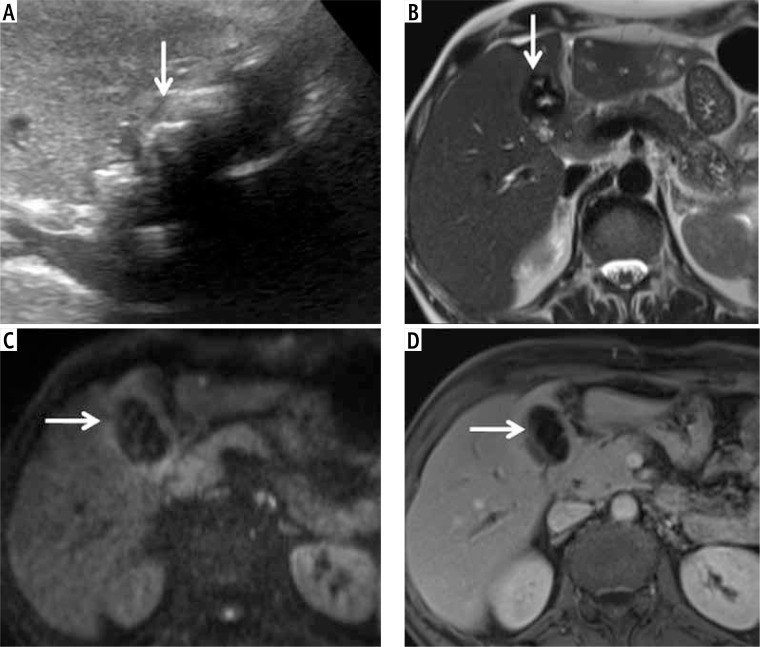

Material and methods: Consecutive patients with non-diagnostic US due to calculi within the gallbladder lumen, obscuring the detailed evaluation, were identified by a research fellow from a prospective database of patients with gallbladder lesions. The US reports and images were evaluated by a radiologist blinded to the final diagnosis. Patients who had the final pathological diagnosis based on fine-needle aspiration cytology, percutaneous or endoscopic biopsy, or surgical histopathology were included. Convolution neural networks (ResNet50, GBCNet), transformer models (vision transformer [ViT], RadFormer), and a hybrid model (MedViT) were trained on a public gallbladder dataset (GBCU dataset). The performance of these models for classifying gallbladder lesions into benign and malignant was tested on non-diagnostic (GB-RADS 0) US images.

Results: Training and validation cohorts (GBCU dataset) comprised 1004 and 251 images, respectively. The testing data (26 patients, mean age [SD]: 57.5 ±8.07 years, 17 female) comprised 304 images. The best performance for detection of GBC was achieved with GBCNet (sensitivity 51.1%, specificity 83.3%, area under the curve [AUC] 0.709) and MedViT (sensitivity 92.8%, specificity 50%, AUC 0.714). MedViT had the best accuracy (73.1%) for detecting benign gallbladder lesions.